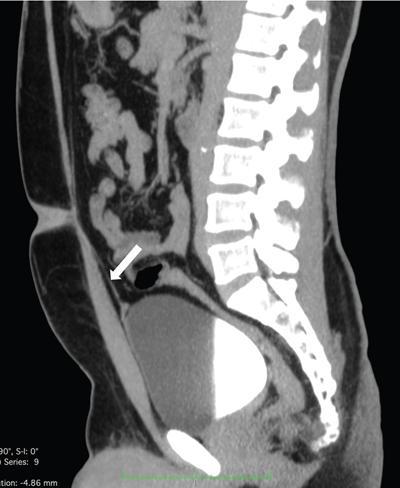

The urachus or the median umbilical ligament is developmentally the obliterated remnants of the allantois and the cloaca. It extends from the dome of the urinary bladder to the umbilicus in the midline (Fig. 10.13.1). It lies in the retropubic space of Retzius in between the transverse fascia and the parietal peritoneum and is extraperitoneal in location.

Image

Fig. 10.13.1 Sagittal CT image showing the normal median umbilical ligament-obliterated urachus (white arrow).